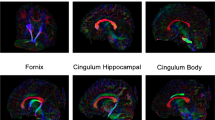

ROI analysis and DTI template

We used the ICBM-DTI-81 (International Consortium of Brain Mapping) atlas as a template (http://www.loni.ucla.edu/Atlases/). ICBM-DTI-81 is a white matter atlas based on probabilistic tensor maps obtained from 81 normal right-handed adults (18 ≤ age ≤ 59, 39 females). Three main regions (splenium, body and genu) of the corpus callosum were selected amongst the 50 white matter tract labels of the atlas. The body of the corpus callosum was further sub-divided (antero-posterior dimension) in three regions according to the modified Witelson scheme defined earlier [20] (Fig. 1). From posterior, these regions are the isthmus (IV) with posterior parietal, superior temporal projections, the posterior midbody (III) with primary motor cortex projections and the anterior midbody (II) with projections to the premotor and supplementary motor cortical areas [20]. This subdivision of the body is illustrated in Fig. 1 and was further limited to x = [−12; 12] mm in lateral dimension. The FA maps in patients were compared with those in controls using Mann–Whitney test. This non-parametric test was justified because of the relatively small sample size in the patient group and the non-Gaussian distribution of the FA values. The threshold for statistical significance was set at p = 0.05 and significance level was corrected for multiple comparison (number of ROIs) using Bonferroni correction.

a Midsagittal view of an example FA map from a control subject. b Lateral view of the (3D) corpus callosum and its subdivisions according to [20]. From posterior to anterior: splenium region (red); body regions including: isthmus region (purple), posterior midbody (blue) and anterior midbody (turquoise); and genu region (grey). White lines represent coronal sections at 5 mm steps. 3D file is also available online at http://brainsenses.x10host.com/ICBM_CC.pdf

The fractional anisotropy map for the midsagittal view of a control subject’s corpus callosum (greyscale ranging from black for FA <0.2 to white for FA = 0.8) is shown in Fig. 1a. Subdivisions of the corpus callosum as defined by Hofer and Frahm [20] is illustrated in Fig. 1b. The most pronounced anisotropy is found in the anterior and posterior regions of the CC with the highest FA values close to 0.8 in the most posterior area. The lowest FA values were between 0.25 and 0.5 and were located in the middle region.

To complement the voxel-based analysis, ROI-based analysis was also performed (see “Materials and methods”). The distribution of FA values is shown in Fig. 4 for the five regions of interest illustrated in Fig. 1 along the antero-posterior dimension of the corpus callosum. All the individuals from both populations are represented (red crosses for controls, blue filled circles for IS patients). We also plotted the average FA values derived from the ICBM-DTI-81 adult template. We found that both for the IS patients and the controls, the overall distribution of FA along the CC followed the profile of the DTI adult template. However, despite the similar pattern of FA in both the patient and control groups, a significantly lower FA in patients was found in the two parts of the midbody (section III; p = 0.0003 and II; p = 0.0002). This pattern corroborates the results observed in the voxel-based analysis (Fig. 3) in which the significant voxels were found in the section II of the partition of the corpus callosum. This region II also shows the maximum statistics for difference between the two populations amongst the region of interests. Note that according to the region of interests analysis, the two subdivisions of the midbody show significantly lower FA in IS than controls. Although, our voxel-based analysis might have failed detecting the effect in the posterior body, taken together both analyses suggest a lower FA in IS than controls in the body of the corpus callosum and especially in its most anterior part.

Distribution of Fractional Anisotropy along the corpus callosum in the 10 IS patients (blue circle for individual subjects) and 49 controls (red crosses for individual subjects). Box plots show the lower to upper quartile values and the median. The black dotted line represents the FA values of the ICBM-DTI-81 adult template

In the present study, we measured DTI-derived quantity along the corpus callosum to evaluate the white matter microstructure in 10 young females with IS as compared to 49 sex-matched controls. We found that the overall distribution of FA along the CC was very similar in both populations. Moreover, it followed the profile derived from the adult ICBM-DTI-81 atlas. However, we found that the body had significantly lower FA in patients with IS than in controls (Figs. 3, 4). In particular, the anterior part of the body (region II) showing a significant difference in both the voxel and ROI-based analyses.